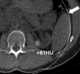

Proteinaceous cyst

Caseous necrosis or caseous degeneration () is a unique form of cell death in which the tissue maintains a cheese-like appearance. It is also a distinctive form of coagulative necrosis. [Source: Wikipedia ]